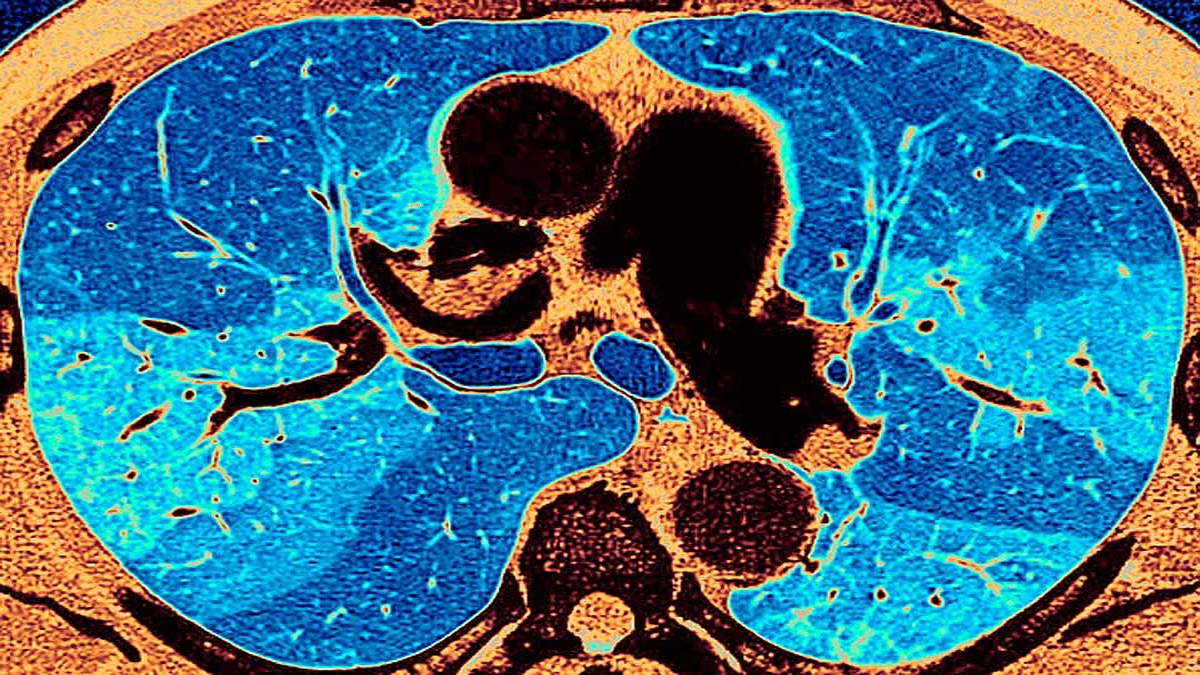

कोरोना वायरस की वजह से भारत, अमेरिका और यूरोप के कई मरीजों में फेफड़ों की एक बड़ी समस्या सामने आ रही हैं. अगर ये समस्या गंभीर होती है तो मरीज की जान भी जा सकती है. कोविड मरीजों को इस फेफड़ों के इस संक्रमण की वजह से थकान रहती है. सांस लेने में काफी दिक्कत होती है. ये समस्या भारत, अमेरिका और यूरोप के कई मरीजों में सामने आई है. (फोटोःगेटी)

कोरोना वायरस की वजह से हो रही इस बीमारी का नाम है लंग फाइब्रोसिस (Lung Fibrosis). इसे पल्मोनरी फाइब्रोसिस (Pulmonary Fibrosis) भी कहते हैं. इसके बारे में एक लेख लंग इंडिया नाम के मेडिकल जर्नल में प्रकाशित हुआ है. इसे लिखा है डॉ. जरीर एफ. उदवादिया, डॉ. परवैज ए. कौल और डॉ. लूका रिडेल्डी ने. तीनों डॉक्टरों ने इसे पोस्ट कोविड-19 इंटरस्टिशियल लंग डिजीस (PC-ILD) कहा है. (फोटोः गेटी)

द इंडियन एक्सप्रेस की खबर के अनुसार पूरी दुनिया में 6 करोड़ से ज्यादा लोगों को कोरोना संक्रमण हो चुका है. इनमें से ज्यादातर हल्के या मध्यम दर्जे के संक्रमण से जूझ रहे हैं. सिर्फ 10 फीसदी को गंभीर कोविड-19 निमोनिया हुआ है. मात्र 5 प्रतिशत लोग ऐसे हैं जो एक्यूट रेस्पिरेटरी डिस्ट्रेस सिंड्रोम (ARDS) नाम की बीमारी से परेशान हैं. यानी यही 5 से 10 फीसदी लोग हैं जिन्हें लंग फाइब्रोसिस (Lung Fibrosis) की शिकायत हो रही है. (फोटोः गेटी)

लंग फाइब्रोसिस (Lung Fibrosis) बीमारी में फेफड़ों के अंदर मौजूद ऊतक यानी टिश्यू (Tissue) सूजने लगते हैं. इसकी वजह से फेफड़ों के अंदर हवा का स्थान कम होने लगता है. नतीजा सांस लेने में दिक्कत होती है. इसकी वजह से इंसान को थकान महसूस होती है. अगर स्थिति ज्यादा गंभीर हो जाए तो मरीज की मौत भी हो सकती है या उसे दिल का दौरा पड़ सकता है. (फोटोः गेटी)

डॉ. उदवादिया ने बताया कि कुछ मरीजों को ठीक होने के बाद भी उनके घर पर भी ऑक्सीजन की जरूरत पड़ रही है. मरीज के ठीक होने के तीन महीने बाद जब सीटी स्कैन किया जाता है तो उनके फेफड़ों की स्थिति बहुत खराब मिलती है. तीन दशक पहले लंग फाइब्रोसिस (Lung Fibrosis) बीमारी आमतौर पर बहुत कम लोगों को होती थी. ज्यादातर बुजुर्गों को होती थी. (फोटोः गेटी)